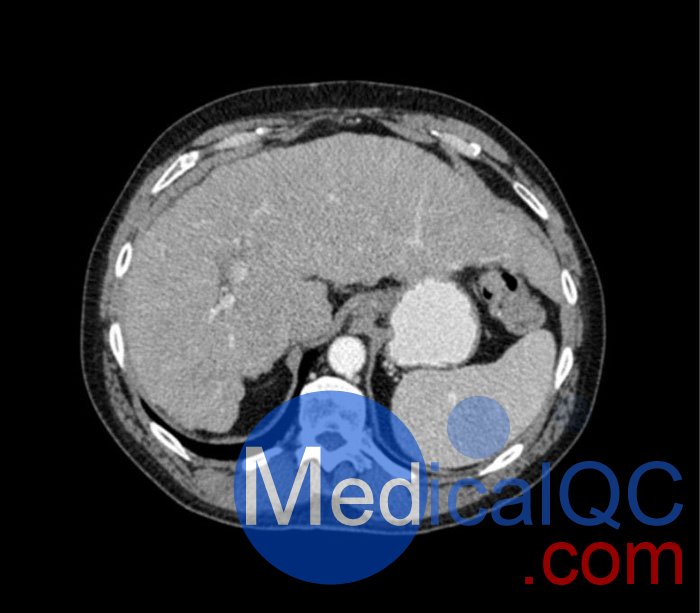

WEK53-04肝硬化腹部模體,WEK53-04腹部模體代表膽囊切除術(shù)后的腹部,帶有小夾子。肝臟有肝硬化的典型體征,在第三腰椎水平植入下腔靜脈過濾器。兩個腎臟都有囊性病變,左側(cè)有一小塊腎結(jié)石。

真實模擬脈管系統(tǒng)、骨骼和軟組織,包括肝臟、胰腺、脾臟、腎上腺、腎臟、胃、小腸和結(jié)腸。

• 肝硬化

• 膽囊切除術(shù)